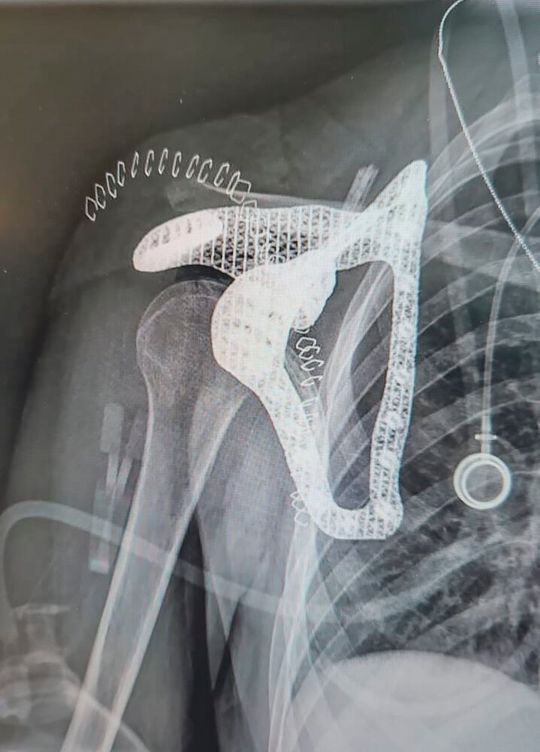

Ein Expertenteam entwickelte gemeinsam ein Scapula-Implantat aus Titan, das exakt auf die Anatomie der Patientin zugeschnitten ist. (Bild:  Tel Aviv Medical Center)

In einem Gemeinschaftsprojekt hat ein Expertenteam des Tel Aviv Medical Center, von PTC und Hexagon ein vollständig patientenspezifisches Scapula-Implantat für eine 16-jährige Krebspatientin geschaffen. Das Team nutzte additive Fertigung und medizinische Bildgebung, um das Implantat aus Titan zu entwerfen und herzustellen, das exakt auf die Anatomie der Patientin zugeschnitten ist.

Die Experten führten eine 3D-Segmentierung des Tumors und des umgebenden Knochens durch, um eine effektive Rekonstruktion zu ermöglichen. Ein digitaler Zwilling des anatomischen Modells wurde erstellt und im Maßstab 1:1 gedruckt, um die präoperative Planung zu unterstützen und die Resektionsränder abzugrenzen. Gleichzeitig wurde mit der CAD-Software Creo von PTC ein individuelles 3D-gedrucktes Implantat entworfen, um die verbleibenden Muskelstümpfe zu verankern und die Gelenke zu rekonstruieren.

• Eine fortschrittliche Gitterstruktur umsetzen, um das Einwachsen von Bindegewebe und Muskeln zu erleichtern und durch Nutzung von Creo Design for Metal Additive Manufacturing Abstützungen und Verzerrungen vermeiden